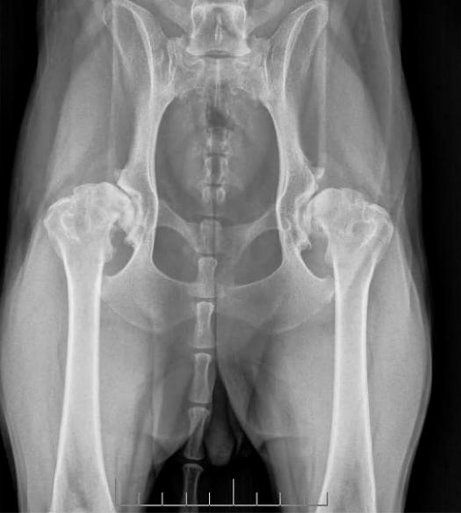

Die Hüftgelenkdysplasie ist die häufigste orthopädische Erkrankung beim Hund und ebenfalls eine sehr häufige bei der Katze. Sie führt durch Laxizität (Lockerheit) und anatomische Fehlentwicklungen zur Osteoarthrose und damit auch zu Schmerzen, Einschränkungen in der Belastung und der Lebensqualität. Die HD ist eine komplexe vererbbare Erkrankung, die durch eine genetische Vorbelastung, entsprechende individuelle- und Umweltfaktoren, wie z.B. der Gelenkflüssigkeit, der Muskelmasse, hormoneller Einflüsse, dem Gewicht, der Wachstumsgeschwindigkeit, der Ernährung und anderer zu klinischen Symptomen führt. Eine zentrale Rolle spielt die Laxizität der Hüftgelenke, die bereits bei Jungtieren nachweisbar ist.

Die HD kann grundsätzlich alle Hunde und Katzen aller Rassen betreffen. Häufig tritt sie bei den Rassen Deutscher Schäferhund, Labrador-/ Golden Retriever, Rottweiler und Berner Sennenhund auf. Klinische Beschwerden können sich sehr unterschiedlich zeigen. Viele Hunde haben Anzeichen chronischer Schmerzen, können schlecht aufstehen, Spielen nicht mehr intensiv oder gehen nur noch kurze Strecken spazieren. Katzen springen zudem ungern. Die Erkrankung verhält sich einheitlich progressiv, d.h. dass die Beschwerden im Laufe des Lebens stärker werden.